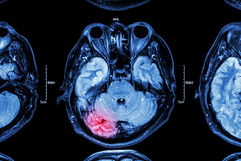

2. AVC hemorrágico

Imagem ilustrativa número 2

Diferente do AVC isquêmico, o AVC hemorrágico não acontece pelo bloqueio de um vaso cerebral, mas sim pelo rompimento de um vaso, o que faz com que o sangue não consiga continuar passando para alguma região do cérebro.  Além disso, no AVC hemorrágico também existe acúmulo de sangue dentro ou ao redor do cérebro, o que aumenta a pressão cerebral, agravando ainda mais os sintomas.